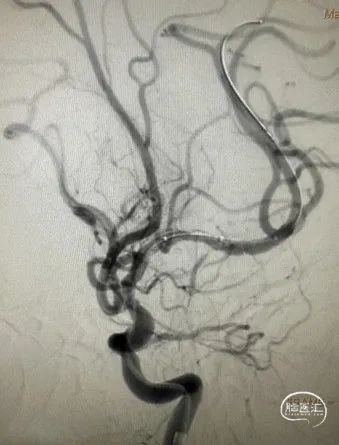

DSA

左侧大脑中动脉重度狭窄,近端:1.78mm,远端:2.18mm,最窄:0.25mm,长度:14.70mm,狭窄率约:89%。

微导丝通过狭窄段到达左侧大脑中动脉远端。

扩张后即刻造影。